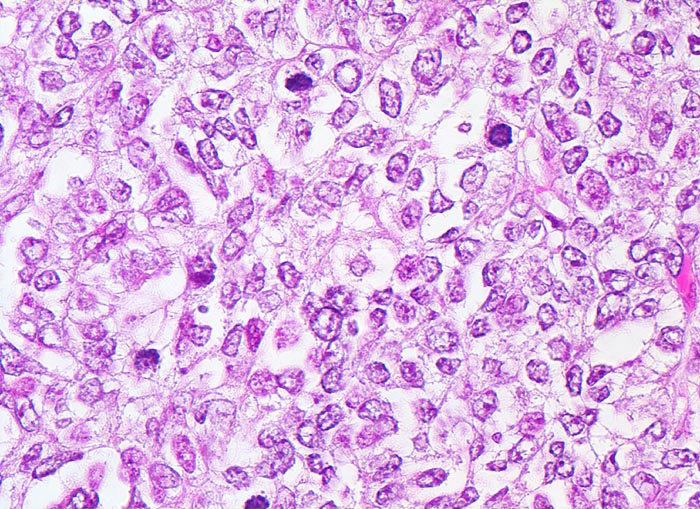

wenig differenziertes endometrioides Adenokarzinom

Solider Tumorzellverband. Die vesikulären (bläschenförmigen) Kerne sind polymorph und hyperchromatisch. Die Kernmembranen sind unregelmässig. Die Kern-Zytoplasmarelation ist erhöht. Mehrere Mitosen.

Exophytischer, in das Uteruscavum hineinragender, weicher fokal hämorrhagischer Tumor ausgehend von der Uterushinterwand. Das Tumorgewebe infiltriert die innere Hälfte des Endometriums.

Postmenopausale Blutung. Diagnose eines endometrioiden Adenokarzinoms in der Corpuskurettage. Daraufhin Hysterektomie, Adnexektomie und Lymphadenektomie.

Histologie

400